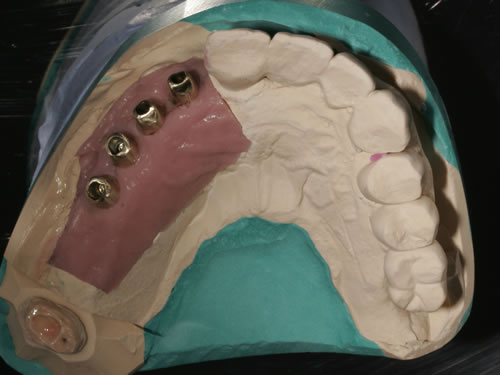

Diese Beispiele ließen sich endlos fortführen. Sie zeigen die Probleme bei der Versorgung zahnloser Kiefer, wie sie immer wieder geschildert werden. Mit Hilfe sehr einfacher Maßnahmen kann durch die Einpflanzung künstlicher Zahnwurzeln eine instabile Prothese soweit befestigt werden, dass die Kau- und Sprechfunktion wieder hergestellt ist. Manchmal kann die alte Prothese weiterverwendet werden, in dem man in die Prothesenbasis Sekundärteile einarbeitet, die für Halt sorgen (Abb. 3.5, 3.6). Bei aufwendigeren Steg- oder Teleskoparbeiten muss auch der Zahnersatz der auf den Implantaten fixiert wird neu angefertigt werden. Diese Arbeiten werden dann brückenartig und sehr grazil gestaltet. (Abb. 3.7 bis 3.12).

Abb. 3.7: Individuelle Stegversorgung aus Stahl auf vier Implantaten im zahnlosen Unterkiefer.

Abb. 3.8: Individuelle Stegversorgung aus Gold auf vier Implantaten im zahnlosen Unterkiefer.

Abb. 3.9: Prothesenansicht von unten mit grazil eingearbeiteten Halteelementen.